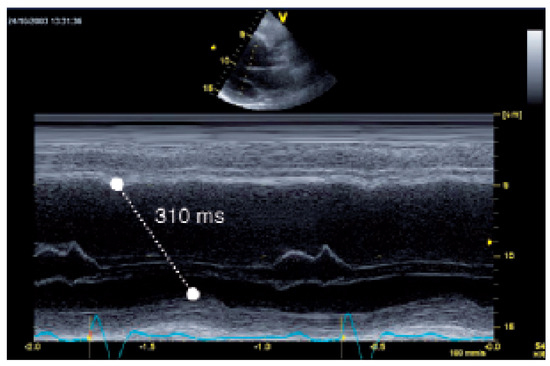

Biventricular pacing is an accepted therapy in patients suffering from terminal heart failure. Main obstacle however is the positioning of the left ventricular electrode via coronary sinus as well as its reliable fixation. This article describes in a...